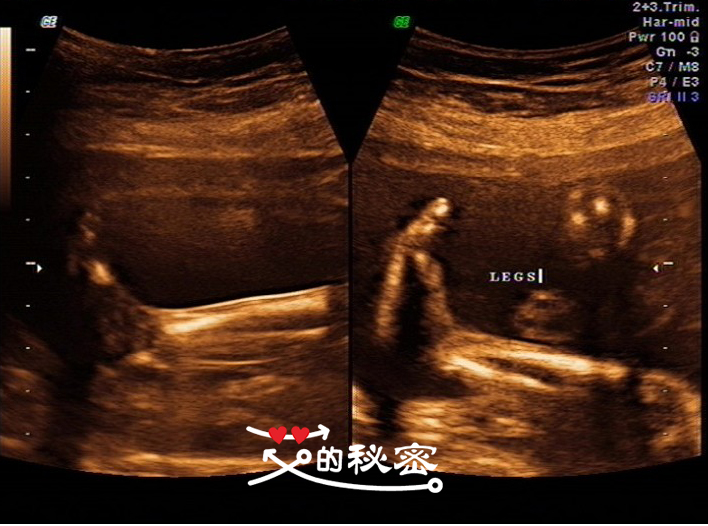

11、胎儿四肢:双侧肱骨、尺桡骨、股骨、胫腓骨可显示,双足可见,双手可见,四肢指(趾)分辨困难,英文FEET双脚,LEGS双腿,ARMS双臂,HAND双手。

5、其它畸形:排查腹部畸形、肢体畸形,先天性心脏病及畸胎病等,通过逐一视察排除胎儿畸形。如图:腿、脚、臂、骨长、心脏等。